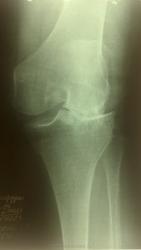

Бабушка 75 лет. Жалобы на боли в суставе. Предыдущих снимков не предоставлено. Со слов на них артроз. На снимках правого сустава Р пр-ки артроза 1 ст.

Значительное сужение суставной щели в наружнем отделе,контактный склероз. Подвывих?

Как с движениями в суставе? Артроз 3 стадии, подвывих. Возможно, боковые связки повреждены.

+ yes Вот хирурги вечно пишут "ДОА" при любых жалобах на боли в суставе. Так ВОТ - плиз:  оно и есть классик-  Деформирующий Остео-Артроз.

Коллеги, если с латеральным мыщелком бедра всё нормально,  по каким признакам артроз 3 ст. - кому авторство этого артроза присуждаете?

Может быть рассекающий остеохондрит(суставная мышь в латеральных отделах) в сочетании с гонартрозом

Мысль про асептический некроз мыщелка бедра посещала меня, но на боковой проекции совсем ровный контур обоих мыщелков, хотя и нечёткий - "мешают" межмыщелковые бугорки. Может, прямую проекцию всё-таки повторим... в должной укладке и без поворотов?)

Спасибо большое за участие. Выяснила,что в анамнезе была травма 10 лет назад с тех пор и беспокоит, в амбулаторной карте ни слова об этом. Посттравматический артроз?

Посттравматический артроз, думаю, и без нас поставят. Мне самому интересно - где та тень, которая на боковом немного... пропала. А Вам не интересно? Повторили бы снимок - развеяли бы сомнения, доказали бы заблуждения...